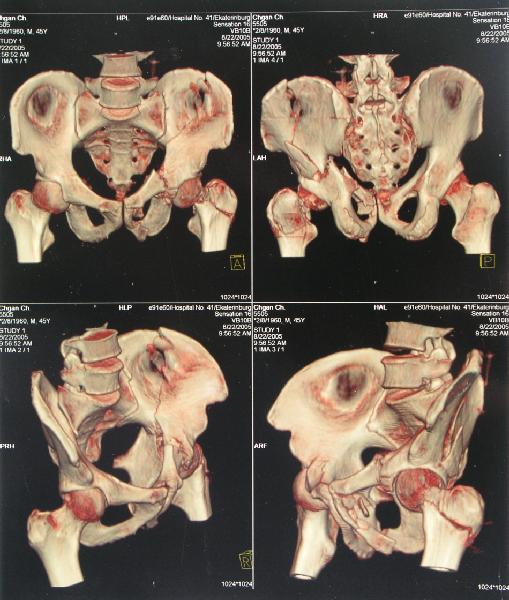

Наш больной пока обследуется, сделали сегодня КТ наконец-то.

Today CT was performed.

Сегодня КТ сделали.